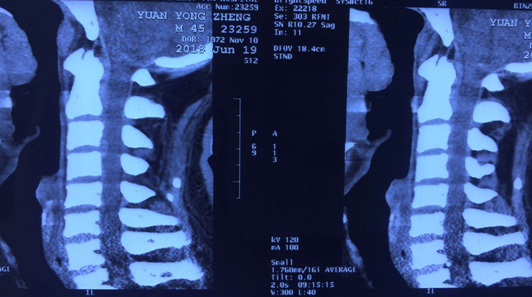

术前CT